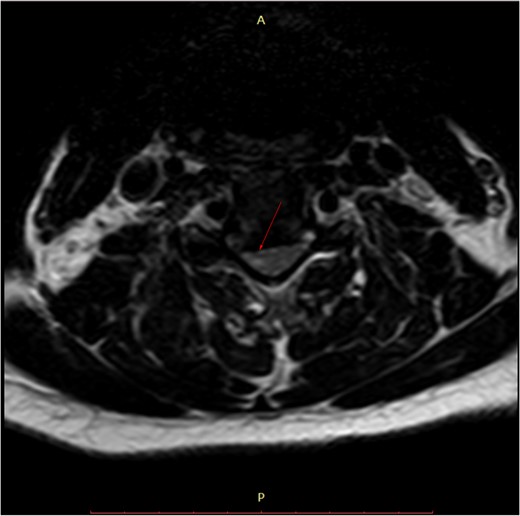

Pre-surgery axial MRI. Arrowhead points towards a focus of hyperintensity at the aforementioned level.